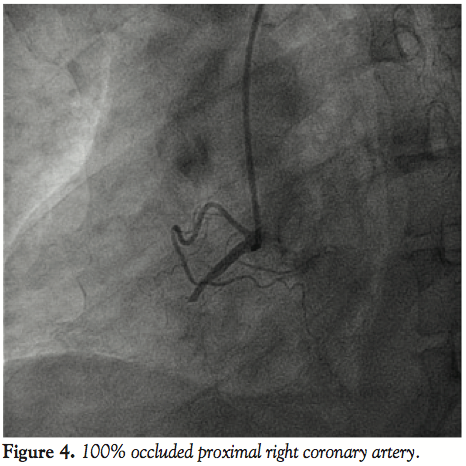

Based on the TEE findings, the patient was referred for cardiac catheterization. The patient was found to have 100% occlusion of the proximal right coronary artery (Figure 4), and subsequently underwent successful restoration of flow with a drug-eluting stent. Follow-up echocardiography 6 months later showed the severity of tricuspid regurgitation had decreased (moderate); however, the RV remained moderately hypokinetic and mildly dilated.